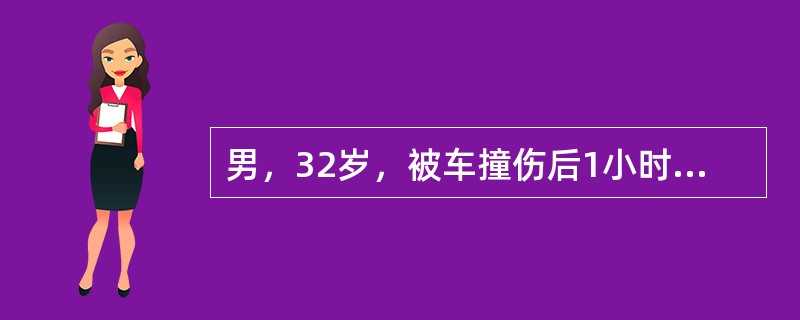

男,32岁,被车撞伤后1小时,请结合影像图像选择其最可能的诊断为()

A.右侧气胸

B.右肺不张

C.右侧气胸并皮下纵隔气肿

D.右侧肺大疱并皮下纵隔气肿

E.支气管断裂

男,32岁,被车撞伤后1小时,请结合影像图像选择其最可能的诊断为()<img style="width: 236px; height: 177px;" src="h

[单选题]男,32岁,被车撞伤后1小时,请结合影像图像选择其最可能的诊断为()A.右侧气胸B.右肺不张C.右侧气胸并皮下纵隔气肿D.右侧肺大疱并皮下纵隔气肿E.

男,32岁,被车撞伤后1小时,请结合影像图像选择其最可能的诊断为()

[单选题]男,32岁,被车撞伤后1小时,请结合影像图像选择其最可能的诊断为()A . 右侧气胸B . 右肺不张C . 右侧气胸并皮下纵隔气肿D . 右侧肺大疱并皮下纵隔气肿E . 支气管断裂

男,32岁,被车撞伤后1小时,请结合影像图像选择其最可能的诊断为()

[单选题]男,32岁,被车撞伤后1小时,请结合影像图像选择其最可能的诊断为()A .右侧气胸B .右肺不张C .右侧气胸并皮下纵隔气肿D .右侧肺大疱并皮下纵隔气肿E .支气管断裂

患者男,32岁,被车撞伤后1个小时急诊行CT检查。结合图像,最可能的诊断为<img border="0" style="width: 316px; height:

[单选题]患者男,32岁,被车撞伤后1个小时急诊行CT检查。结合图像,最可能的诊断为A.右侧气胸B.右肺不张C.右侧气胸并皮下纵隔气肿D.右侧肺大疱并皮下纵隔气

患者男,32岁,被车撞伤后1个小时急诊行CT检查。结合图像,最可能的诊断为<img border="0" style="width: 316px; height:

[单选题]患者男,32岁,被车撞伤后1个小时急诊行CT检查。结合图像,最可能的诊断为A.右侧气胸B.右肺不张C.右侧气胸并皮下纵隔气肿D.右侧肺大疱并皮下纵隔气